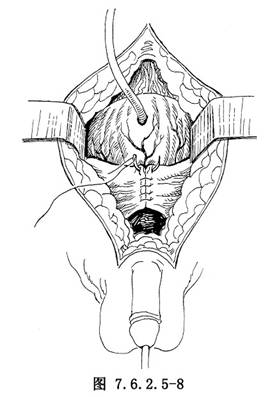

11.7 7.关闭切口,放置引流

尿道内安放导尿管,行耻骨上膀胱造口,缝合耻骨骨膜,耻骨后置橡皮管引流1条,会阴切口置橡皮片引流,逐层关闭切口(图7.6.2.5-8)。